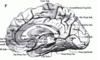

Key gyri on medial view of frontal lobe

Superior frontal gyrus

Paracentral lobule

Cingulate gyrus

Key sulci on medial surface of frontal lobe

Cingulate sulcus